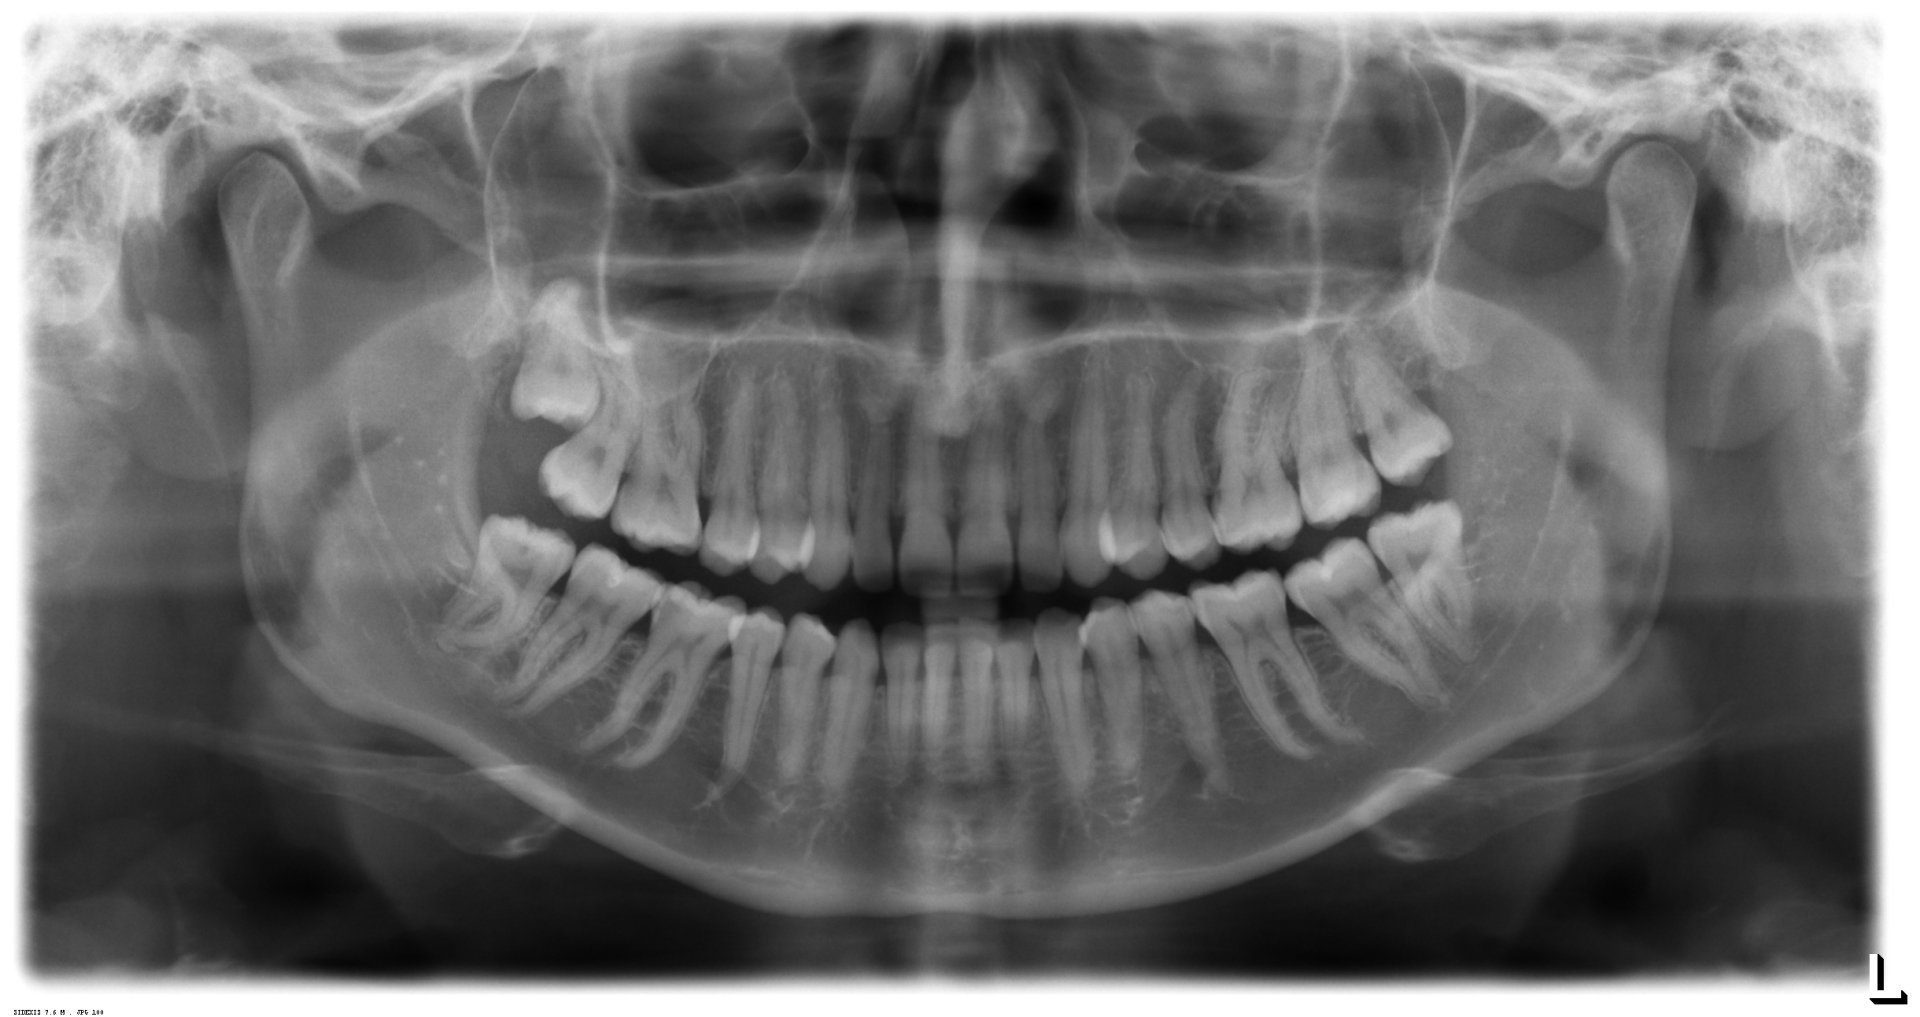

When should wisdom teeth be removed?

cysts

Odontogenic cysts, tumors

Recurrent inflammation

Risk: Life-threatening inflammation

Caries (also on the tooth in front of it)

Tooth decay in wisdom teeth can be difficult and not easy to treat in the long term

Before dysgnathia

The osteotomy leads through the wisdom tooth region